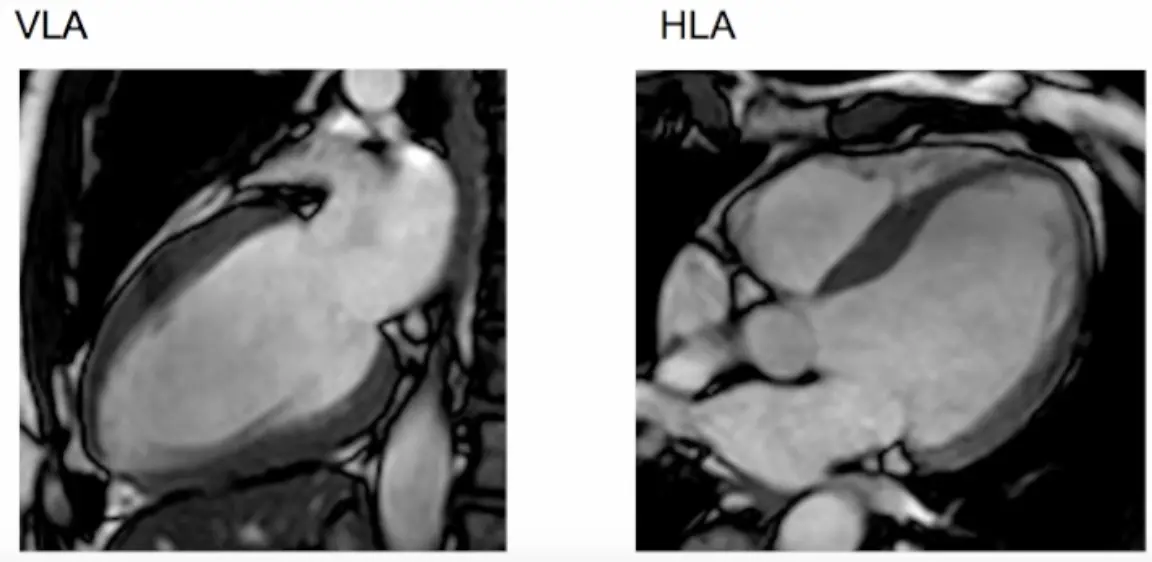

- Step 1. Scouts and planning views (VLA, HLA)

- We begin with the transverse LAX view and position the line marker dissecting the apex and the middle of the mitral valve (where the two leaflets meet) → results in a vertical LAX (VLA) view, aka pseudo 2 chamber (p2CH) view

- Next we slice the resulting VLA view: again, we cut across the apex and the middle of the mitral valve (where the two leaflets meet) → results in a horizontal LAX (HLA) view

- Resulting scout views include VLA and HLA views